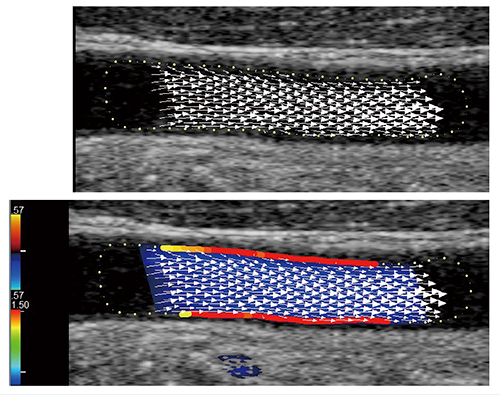

このVFMを血管に応用した“VFM Vascular”は,日立製の超音波診断装置「LISENDO 880LE」に搭載されており,オフラインで短時間での解析が可能である。基本的な原理はVFMと同様であるが,tissue trackingに加えて補助ビームも送受信して真の血流ベクトルを求めて演算開始点を作成し,血流が組織に与える影響を評価する4)。血行動態は,速度ベクトル表示にて可視化できるほか,血管壁のWSSがパスカル(Pa)表示される(図1)。初期検討では,年齢やIMTとの相関も示唆され,IMTが肥厚する以前のより早期の動脈硬化の指標になる可能性があると考えるが,少数例でもあり今後の検討が待たれる。

図1 総頸動脈のVFM Vascular

上段:速度ベクトル表示

下段:カラードプラ表示に加えた速度ベクトルとWSS